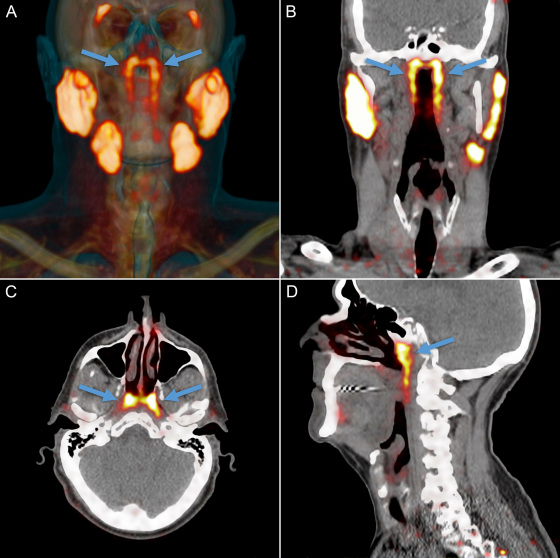

上圖可以看出,新的器官正位於上圖中箭頭標註的發光的地方,其他發光的地方就是我們以前認為的唾液腺所在的位置。

研究小組起初是通過放射性示蹤劑來研究前列腺癌的,這種放射性示蹤劑在進入人體以後會與前列腺癌細胞中的蛋白質PSMA (前列腺特異性膜抗原)結合,這其實就是癌細胞被標記的過程。

然後通過掃瞄追蹤放射性示蹤劑我們就能知道癌細胞的位置,這種利用示蹤劑成像診斷法被稱為“PSMA PET-CT”。

不過PSMA這種蛋白質不僅存在於前列腺癌細胞中,在人體的唾液腺阻止中也存在,因此在掃瞄成像的過程中就標記出了人體中所有唾液腺的位置。

也正是通過以上的方法, 研究小組意外的發現了新的唾液腺,並且把這種新發現的器官命名為“Tubarial Glands (管狀腺)”